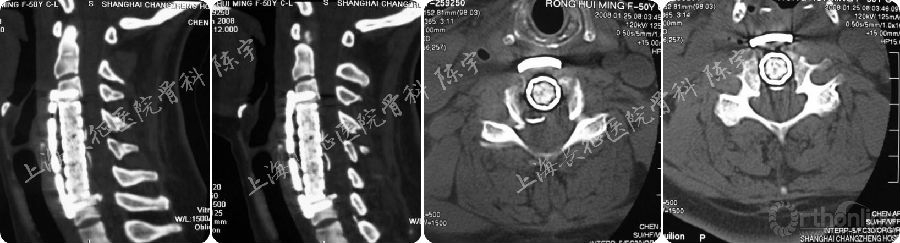

(3) 颈椎后纵韧带骨化合并硬膜囊骨化的诊断与手术技术:在颈椎后纵韧带骨化前路手术中,常常会遇到合并硬膜囊骨化的情况,如未作充分准备极易导致脑脊液漏甚至神经损伤的严重并发症。日本学者最早报道采用CT“双影征”进行诊断合并硬膜囊骨化,后纵韧带骨化物与硬膜囊骨化之间由未骨化的后纵韧带组织分隔形成CT“双影征”。在我们的一项研究中,CT“双影征”对合并硬膜囊骨化诊断的特异性为96.9%,敏感性为55%[6]。

对于此种情况,术中使用磨钻将骨化物磨至薄薄一层,而后使用神经剥离子在韧带和硬膜囊间寻找“安全间隙”进行分离,并切除骨化韧带,保留硬膜囊骨化(图6)[7]。但未骨化的韧带可能会随着OPLL程度的加重而消失,而此种情况则无法分离切除,前路手术风险较大。